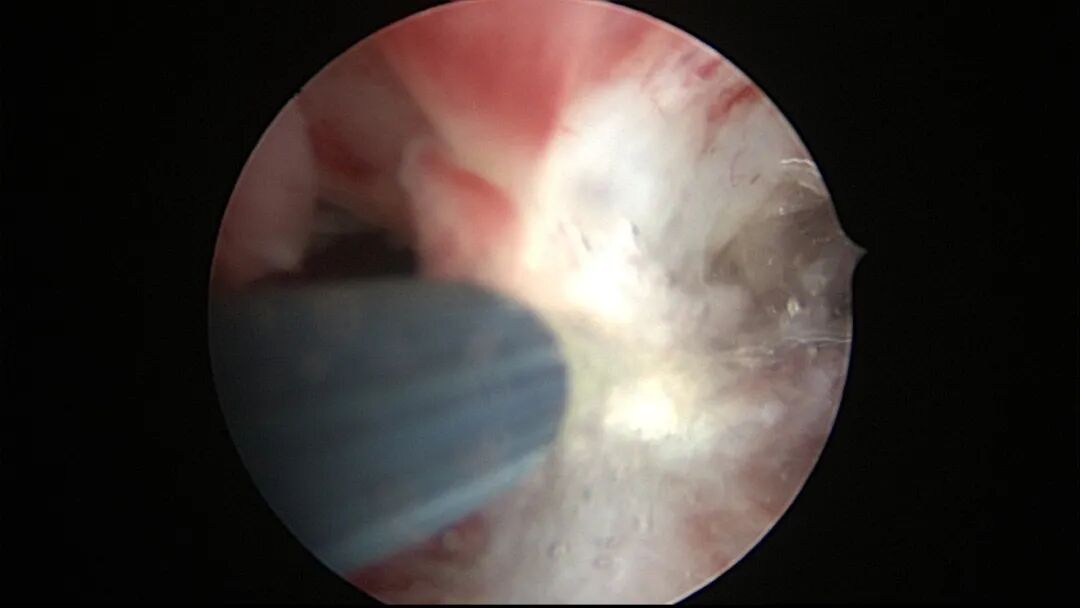

第一次宫腔镜:2021年4月,闭经50+天,B超提示宫腔粘连,宫腔镜探查见宫颈管上段封闭粘连,宫腔广泛粘连,AFS评12分(最高分)。宫腔镜单极电切分粘,恢复宫腔形态,显露双侧输卵管开口,右侧宫角附近内膜柔软、红润,宫腔防粘连复发处理。